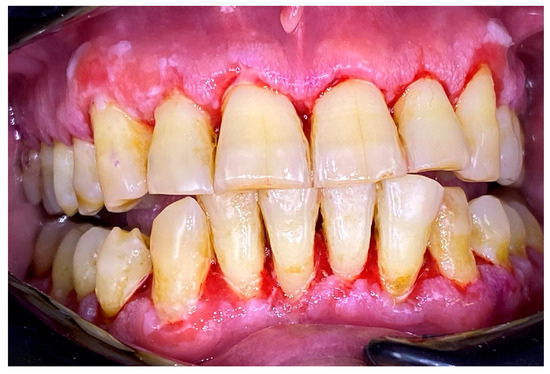

2.3. Clinical Case 3—Oral Lichen Planus (OLP)